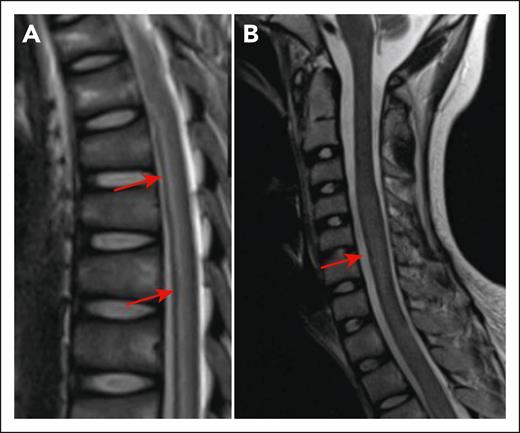

Myelitis following CD19 CAR T cells. (A) Longitudinally extensive T2 hyperintensity in the spinal cord of a 13-year-old presenting with bilateral leg weakness in the setting of CRS and ICANS (day 10 after CD19 CAR T-cell infusion). Arrows show areas of hyperintensity. (B) Increased expansion of the spinal cord T2 signal on day 21 after CAR T. The arrow shows increased expansion of the spinal cord. The figure has been adapted from Figure 1I,K in the article by Diorio et al that begins on page 1387.

The American Society for Transplantation and Cellular Therapy’s definition of ICANS includes “deep focal motor weakness such as hemiparesis or paraparesis,” regardless of where in the nervous system the injury localizes.2 Recent reports of myelitis in adults with B-cell lymphoma receiving CD19 CAR T cells, who have inflammation and swelling of the brain stem extending into the spinal cord, demonstrate extension of ICANS beyond the brain.3-5 Accordingly, when myelitis arises with severe cytokine release syndrome (CRS) or ICANS, it is highly suspicious for relatedness to CAR T-cell treatment, especially if there are simultaneous imaging abnormalities in the brain or brain stem. In these cases, spinal cord injury likely represents the same underlying pathophysiology as “typical” ICANS. This exact pattern of injury was seen in 1 patient in this series, who after infusion of CD19 CAR T cells developed bilateral flaccid leg weakness with concurrent grade 4 CRS and ICANS with severely depressed mental status (see figure). As identifying paresis in critically ill patients can be challenging, it may not become apparent until the mental status improves. Thus, in severe CRS/ICANS, a heightened index of suspicion and early involvement from neurology for close monitoring is critical for quickly identifying and addressing progressive central nervous system (CNS) toxicity.